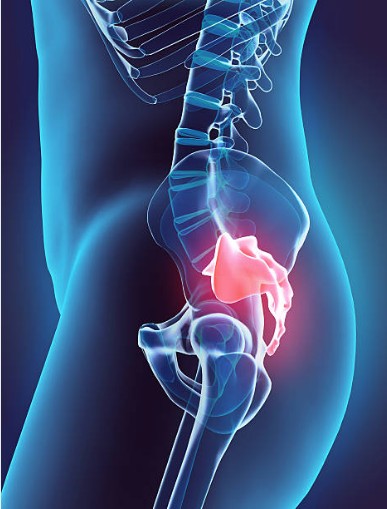

안녕하세요. 오늘은 꼬리뼈가 아픈 이유와 해결방법에 대해 알려드리겠습니다. 꼬리뼈는 인간의 두개골의 일부로서, 골반과 연결되어 있습니다. 꼬리뼈는 체중을 지탱하고, 앉아 있을 때 충격을 흡수하는 역할을 합니다. 그러나 꼬리뼈에 통증이 생기면 일상생활에 많은 불편함을 겪을 수 있습니다. 이 글에서는 꼬리뼈가 아픈 이유를 5가지로 분류하고, 각각의 증상과 원인, 그리고 효과적인 해결방법을 소개해드리겠습니다.

꼬리뼈가 아픈 가장 흔한 원인은 외상이나 부상입니다. 넘어지거나 엉덩방아를 찧거나, 자전거나 오토바이를 타다가 사고를 당하는 등의 경우에 꼬리뼈에 충격이 가해져서 염증, 타박상, 골절, 금 등이 발생할 수 있습니다. 이런 경우에는 꼬리뼈에 심한 통증을 느끼게 되며, 서있거나 앉아 있거나 걷는 것도 어렵게 됩니다.

임신이나 출산은 여성의 몸에 많은 변화를 일으킵니다. 임신 중에는 자궁이 커지면서 골반과 척추에 압력이 가해지고, 출산 시에는 아기가 산도를 통과하면서 꼬리뼈와 주변 조직에 큰 힘을 주게 됩니다. 이런 과정에서 꼬리뼈가 손상되거나 이동되면서 통증이 발생할 수 있습니다.

과체중이나 지방부족은 꼬리뼈에 문제를 일으킬 수 있습니다. 과체중인 경우에는 꼬리뼈에 지속적인 압력이 가해져서 통증이 발생할 수 있습니다. 지방부족인 경우에는 엉덩이에 충분한 쿠션 역할을 하는 지방이 없어서 꼬리뼈가 주변 조직과 마찰되어 통증을 유발할 수 있습니다.

잘못된 자세는 꼬리뼈에 악영향을 줄 수 있습니다. 장시간 의자에 앉아 있거나, 짝다리를 짚고 서 있거나, 몸을 구부리거나 비틀거나 하는 등의 잘못된 자세가 습관화되어 있다면 꼬리뼈가 한 쪽 방향으로 틀어지거나 뒤틀릴 수 있습니다. 이렇게 되면 균형감각이 상실되고, 근육과 인대가 손상되어 통증이 발생할 수 있습니다.

꼬리뼈 통증의 원인은 위에서 소개한 것 외에도 다양한 질환으로 인해 발생할 수 있습니다. 예를 들어, 골다공증, 골관절염, 척추염, 골수염, 골암, 난소낭종, 자궁근종, 자궁내막증 등의 질환들은 모두 꼬리뼈 통증을 유발할 수 있습니다. 이런 경우에는 꼬리뼈 통증 외에도 다른 증상들이 동반될 수 있으므로, 정확한 진단과 치료가 필요합니다.